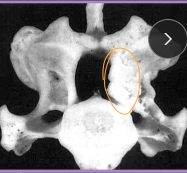

Lumbosacral Disease (Cauda Equina Syndrome)

Et: L7-S1/3 → spinal cord stops @ L5-6

Degenerative: disc protrusion, lig hypertrophy, facet hypertrophy, spondylosis, instability

Dt: rads (spondylosis, narrowed disc), CT, MRI(best)